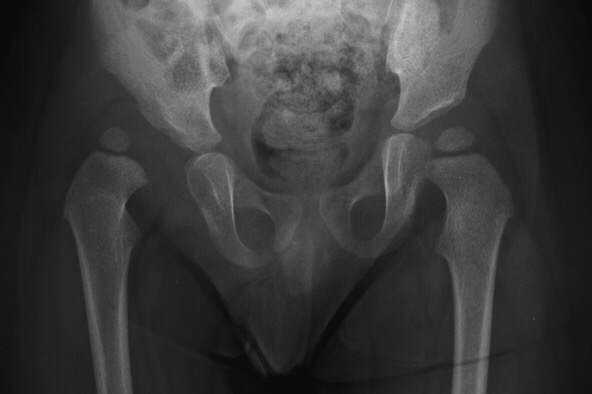

My name is Matías Leonardo Sibila Vargas, I am 22 monthsold and I live with my parents in Venezuela. I was recently diagnosed with a developmental dysplasia of my right hip bone with reducible and unstable variation. In order to walk properly for the rest of my life I have to go through a surgical procedure as soon as possible, otherwise I will live with a permanent disability and the symptoms are going to get worse and worse. Right now my posture is unstable and, although I can walk, it is very difficult for me to maintain a straight posture and I lose my balance very often.